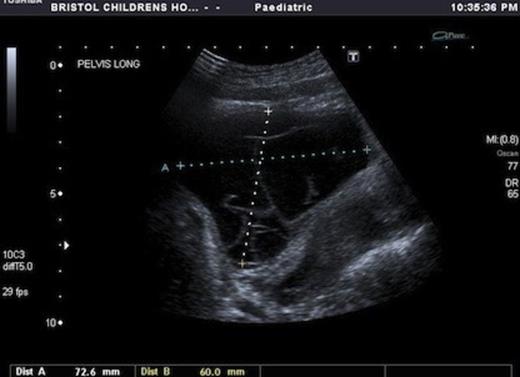

USS showed a septated cystic structure behind the bladder and abutting the ovary. There was echogenic fluid within the cysts. (Fig 1&2)